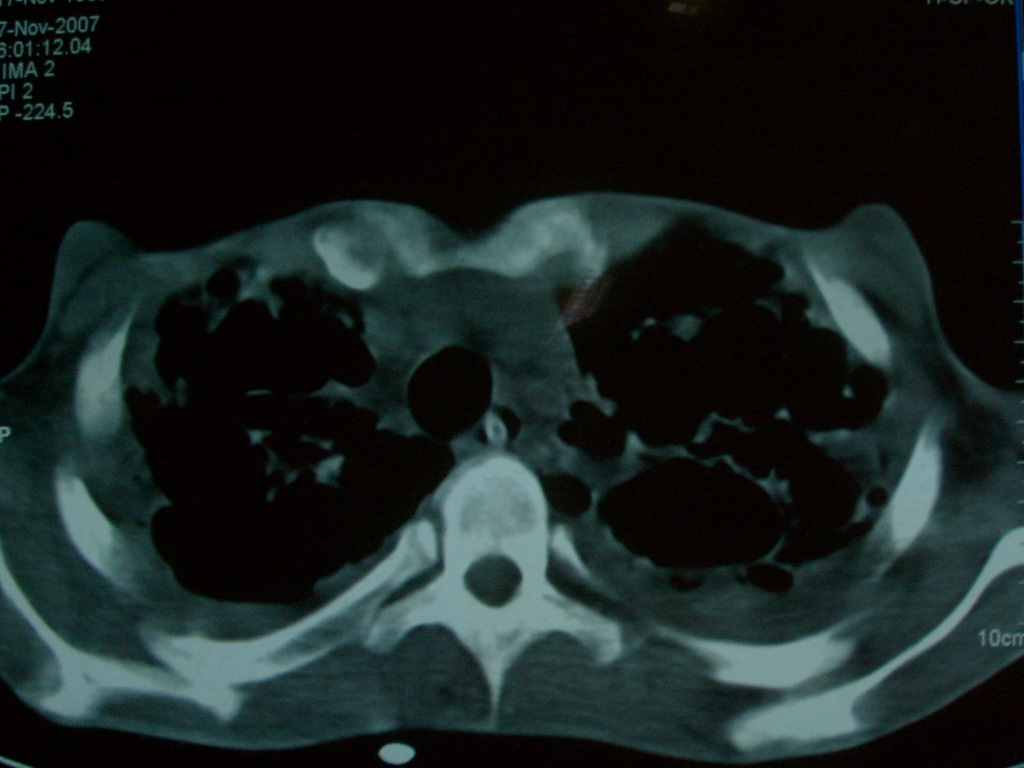

标题: CT10510:男.18岁,咳嗽咳痰两月.(有病理) [打印本页]

标题: CT10510:男.18岁,咳嗽咳痰两月.(有病理)

双肺布满大片状实变及网格状结节影,内参杂大小不等的气囊及空气支气管征,双侧胸膜腔少量积液,双下肺近膈面透亮度尚可,病人较年轻,病变较重(不知为什么上胃管?)考虑:1.胶原病肺部改变,2.组织细胞病x。结合实验室检查。

首先考虑组织细胞x病。两肺中上肺野多发囊腔,中下肺野内见多发小结节,并可见肺间质增厚。患者是男性,年龄较小。胶原性病变比较多见的类风湿、系统性红斑狼疮和硬皮病临床和影像均不是很支持,类风湿和系统性红斑狼疮的肺部表现最常见的是胸腔积液,硬皮病可见食管的扩张。

肺内多发斑片状、结节状、融合大片状及网格状影,多发薄壁空腔影,胸膜肥厚,纵隔、气管右移,考虑ⅲ型肺结核,多发空洞,继发肺间质纤维化。

双肺结核并播散.患者以肠梗阻入院,手术为肠结核.术后咳嗽做ct检查.